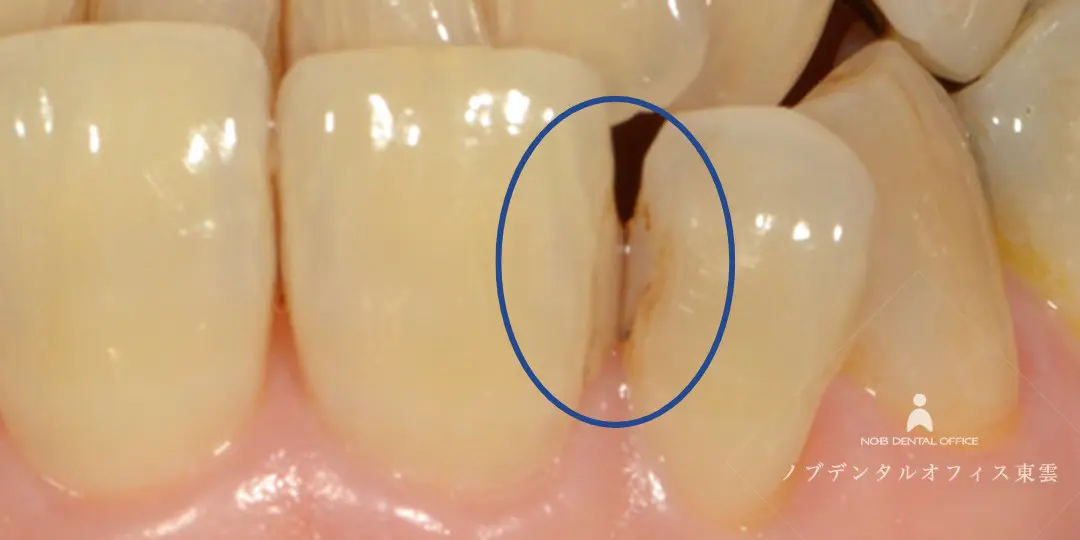

「前歯の虫歯を治したい」とご来院されました。

診察の結果、歯と歯の間に二次う蝕(虫歯)を確認。

2本とも虫歯になっており、同時に治療し、1日で完了しました。

虫歯になっている箇所を削り、CR(コンポジットレジン)充填まで1日で完結しました。

患部を削った様子。

ラバーダムを装着し、マイクロスコープで拡大しながら、患部を削ります。

健康な歯はできるだけ削らないよう配慮します。歯を大切に残したい人に優しい治療です。

自費で使えるCRは特別なエッチング処理と3ステップの接着をするため、再発防止・境目の着色抑制効果があります。